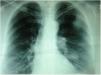

Radiografía posteroanterior de tórax. Se visualizan 3 lesiones nodulares sin broncograma aéreo, de 2–3cm de diámetro, localizadas en el hemitórax izquierdo; 2 adyacentes situadas en el lóbulo superior izquierdo, periféricas, y otra central y parahiliar en el lóbulo inferior del mismo lado.

La neumonía redonda (NR) es una causa muy infrecuente de nódulo pulmonar solitario, más aún en adultos, y raramente puede presentarse como nódulos múltiples y simular una afectación tumoral difusa del parénquima pulmonar. Presentamos el caso de una mujer de 56 años, con antecedentes de asma bronquial y fumadora de 50 cigarrillos/día. Acudió a nuestro hospital con clínica de 5 días de evolución de dolor pleurítico en el hemitórax izquierdo, tos seca, sudoración nocturna, fiebre elevada, astenia y pérdida de peso de 2 kg en este tiempo. El examen físico general fue normal, salvo por la auscultación de algún crepitante aislado en el hemitórax izquierdo. No había signos de cianosis, acropaquias ni adenopatías a ningún nivel. La clínica y los parámetros hematológicos y bioquímicos apoyaban la etiología infecciosa: leucocitosis (15.800/mm3), elevación de la proteína C reactiva (33,4UI) y velocidad de sedimentación globular (62mm/h), pero la radiografía de tórax reveló la presencia de varios nódulos pulmonares, por lo que se decidió su ingreso para estudio de las lesiones descritas con objeto de descartar un origen neoplásico. Igualmente se inició tratamiento antibiótico oral con levofloxacino (500mg/24h) y se solicitó una TC de tórax. Se amplió el estudio con pruebas microbiológicas, marcadores tumorales e inmunología, que resultaron todas negativas, salvo la antigenemia en orina, que reveló positividad para neumococo. Dos días después de su ingreso se constató mejoría de la clínica respiratoria. Posteriormente, en el séptimo día de ingreso, se solicitó un nuevo control analítico y radiológico donde se pudo comprobar la normalización de los parámetros sanguíneos alterados y la resolución de los nódulos pulmonares, hecho que confirmó la TC, en la que no se evidenciaron las lesiones descritas ni adenopatías a ningún nivel. Se mantuvo el tratamiento antibiótico hasta completar 10 días y se decidió el alta médica de la paciente y su seguimiento ambulatorio en consulta. A la vista de los resultados, la paciente se diagnosticó de una NR de localización múltiple por neumococo. Seis meses después del episodio, la paciente continúa asintomática, las pruebas hematológicas son normales y no hay evidencia radiológica de recidiva (fig. 1).